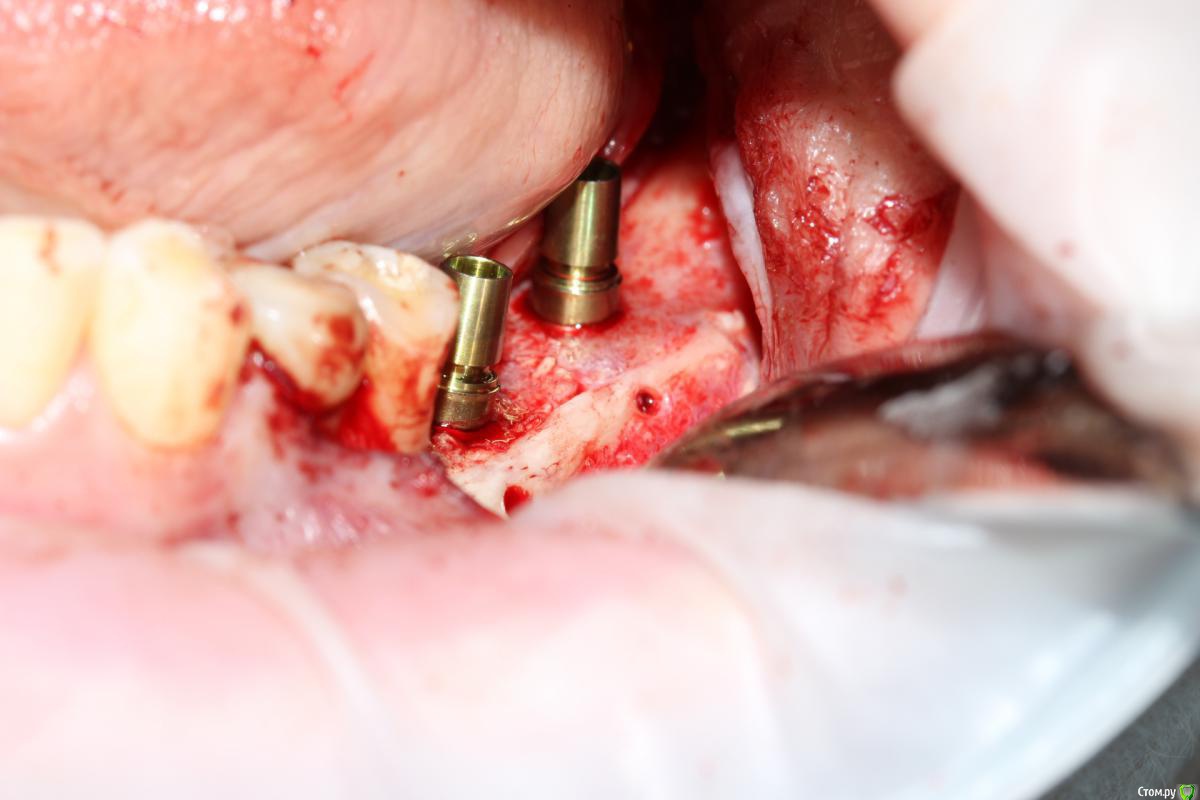

Dantist55 Опубликовано 22 декабря, 2014 Поделиться Опубликовано 22 декабря, 2014 Извиняюсь за фото, над фотопротоколом работаю. Критика приветствуется. 17 Ссылка на комментарий

Sahan Опубликовано 22 декабря, 2014 Поделиться Опубликовано 22 декабря, 2014 В четвертом сегменте во время имплантации дополнительно костную пластику проводили? Ссылка на комментарий

Mane Опубликовано 22 декабря, 2014 Поделиться Опубликовано 22 декабря, 2014 в целом хорошо. но нет деталей где я смогу понять что качественно отработали: 1) кт срезы до и после с замерами чтоб было понятно на сколько нарастили 2)кт срезы с установленными имплантами чтоб было понятно какие болты удалось установить и стало чтоб всем понятно для чего наращивали - ведь вы растили в высоту и в ширину. 3) фото на этапе установленных имплантов - соотношение платформы импланта и уровня кости - заглубили или нет - если да то насколько. Ориентировались ли на будущий зенит зуба. мне понравилось. но чуйка что есть гиперлечение - думаю можно было болты и костную пластику совместить. Растить по высоте я скорее всего бы не стал. 1 Ссылка на комментарий

Dantist55 Опубликовано 22 декабря, 2014 Автор Поделиться Опубликовано 22 декабря, 2014 В четвертом сегменте во время имплантации дополнительно костную пластику проводили?Да, имплантация с НКР. Ссылка на комментарий

Dantist55 Опубликовано 22 декабря, 2014 Автор Поделиться Опубликовано 22 декабря, 2014 в целом хорошо. но нет деталей где я смогу понять что качественно отработали: 1) кт срезы до и после с замерами чтоб было понятно на сколько нарастили 2)кт срезы с установленными имплантами чтоб было понятно какие болты удалось установить и стало чтоб всем понятно для чего наращивали - ведь вы растили в высоту и в ширину. 3) фото на этапе установленных имплантов - соотношение платформы импланта и уровня кости - заглубили или нет - если да то насколько. Ориентировались ли на будущий зенит зуба. мне понравилось. но чуйка что есть гиперлечение - думаю можно было болты и костную пластику совместить. Растить по высоте я скорее всего бы не стал.КТ посмотрю позже на работе - я в отпуске.По высоте добавляли чтобы зубы не получились большими.Импланты не заглублял, т.к. у XIVE полированная фаска.Насчет гиперлечения может Вы и правы. Эту работу я сделал сразу после приезда от Кури. 2 Ссылка на комментарий